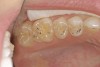

The teeth themselves often can be full of diagnostic information. Is there excessive tooth wear (Figure 7 through Figure 9)? Is there excessive mobility in any teeth? Is there unwanted migration of teeth? Is there a centric relation/maximum intercuspation discrepancy (hit on inclines and slide into full intercuspation) (Figure 3)? If there is a discrepancy, is the deviation in the arc of closure or line of closure? Is the patient able to chew all types of food on both sides without pain? Does the patient feel like their bite is changing or unstable? In addition, are there functional patterns evident by the wear present on the teeth. For instance, horizontal bruxers (Figure 10) often have flat tabletop wear present. Vertical, constricted wear patterns (Figure 11) often have anterior chipping and lingual wear of maxillary anterior teeth.

CLINICAL EXAMPLES (9.) Posterior dentinal exposure is a sign of occlusal instability; this exposure will only get worse if the cause is not resolved and the tooth restored. (10.) An example of a horizontal functioning patient; note the flat “table-top” wear patterns.

Figure 9  CLINICAL EXAMPLES Posterior dentinal exposure is a sign of occlusal instability; this exposure will only get worse if the cause is not resolved and the tooth restored.

Figure 9